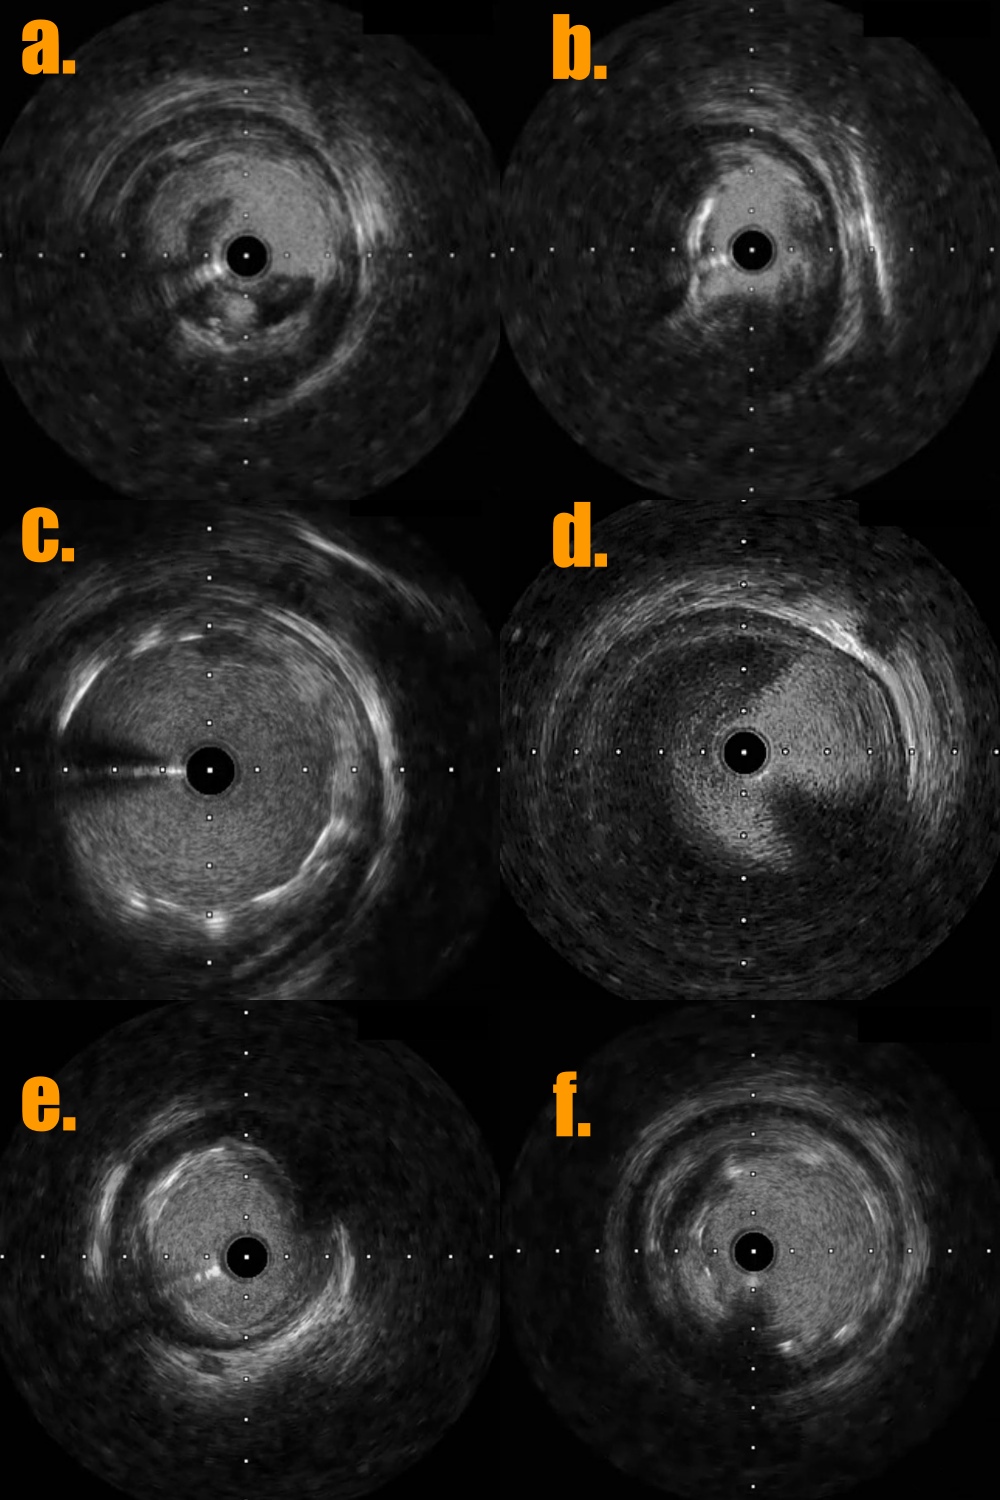

1. The 7 Fr left side radial sheath (Terumo; Glidesheath) was via left side radial artery approach and the guiding catheter was JR4 (Medtronic 7Fr) and the workhorse guidewire was Sion blue.2. Predilatation of the stenoses of distal part and middle part of RCA by the baloon Euphora 2.5x20mm and then IVUS was performed to assess the high risk plaque with adjacent CAE at middle RCA (Fig 5a and 5b) and stable plaque with adjacent CAE thrombus at distal RCA (Fig 5d and 5e).3. PCI of high risk plaque of middle RCA by direct DES stenting of Megatron (Boston ; 4.5x 12mm) under the extra-support of the guiding extension catheter of Telescope (Medtronic; 7 Fr) and lesion post-dilatation by larger balloon of NC Emerge (6.0x12mm) with 14 bars (Fig 6).

4.. PCI of distal RCA lesion first by direct drug-eluting stent (DES) Ultimaster-Nagomi (Terumo; 4.0x15mm) and then post-dilatation by larger balloon NC Emerge (6.0x8mm) with 16 bars. There was coronary thrombus at coronary ectasia of distal RCA with slow distal flow (Fig 5d). The intra-coronary thrombus suction device of Export Advance (Terumo; 6 Fr) was into CAE site of distal RCA for maneuver thrombus suction several times but still residual thrombus at CAE (Fig 6).

5. The final coronary angiogram of RCA has good distal flow (video 3) with stent optimalization (Fig 5c and 5f)